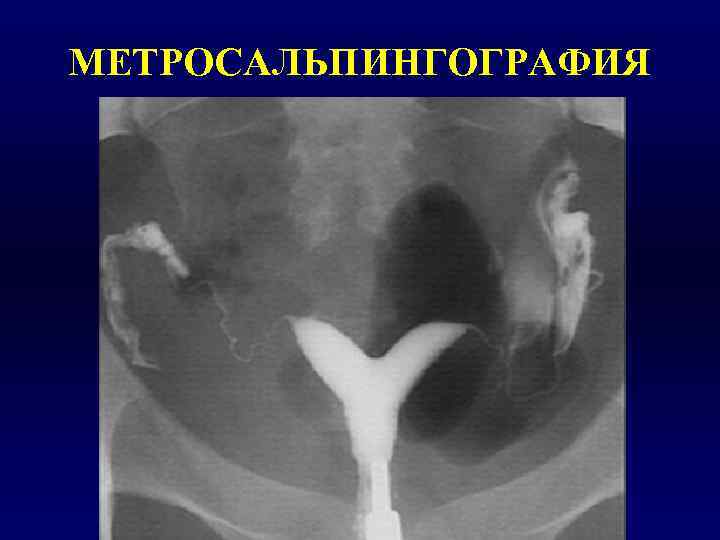

Гистеросальпингография: описание и фотографии